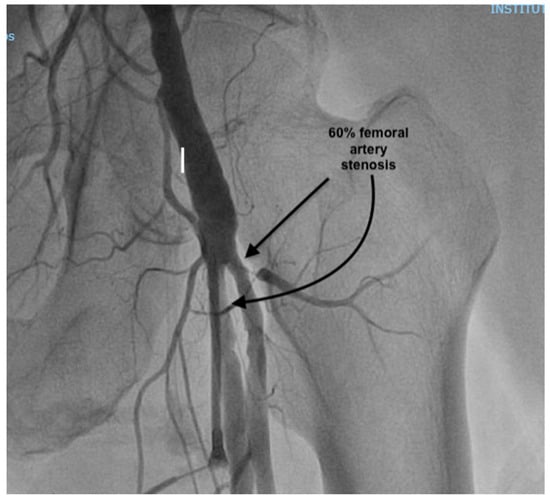

At presentation, the patient was in cardiogenic shock, at Society for Cardiovascular Angiography and Interventions (SCAI) stage C, with acute pulmonary edema: he was dyspneic, with a breathing rate of 25/min; an SpO2 of 90% under 6 L/min of oxygen, with diffuse fine crackles in both lungs; a blood pressure (BP) of 120/80 mmHg; a heart rate of (HR) 120/min; warm, but clammy skin; and a serum lactate of 2.5 mmol/L. He had a loud holosystolic murmur at cardiac auscultation. The ECG showed inferior ST-elevation myocardial infarction (STEMI), and the fast trans-thoracic echocardiography (TTE) showed moderate left ventricular (LV) dysfunction, with an ejection fraction (EF) of 40%, a moderate MR (vena contracta 6 mm), and a large VSD (2 cm), with left-to-right shunting. The patient was taken to the cardiac catheterization laboratory, where a right coronary artery (RCA) sub-occlusion was diagnosed (Figure 1), with no other hemodynamically significant coronary lesions. During the procedure, the patient was managed using non-invasive pressure-support mechanical ventilation (NIV) due to aggravated dyspnea and orthopnea. Interventional revascularization was not possible or indicated due to the distal lesions, with TIMI II flow, and the lack of benefit in an already non-viable myocardial territory. Despite significant PAD of the left inferior limb (Figure 2), an intra-aortic balloon pump (IABP) via the superficial left femoral artery was placed immediately.

Figure 2. Peripheral angiography prior to IABP placement, showing 60% stenosis of superficial femoral artery and profonda femoris artery.